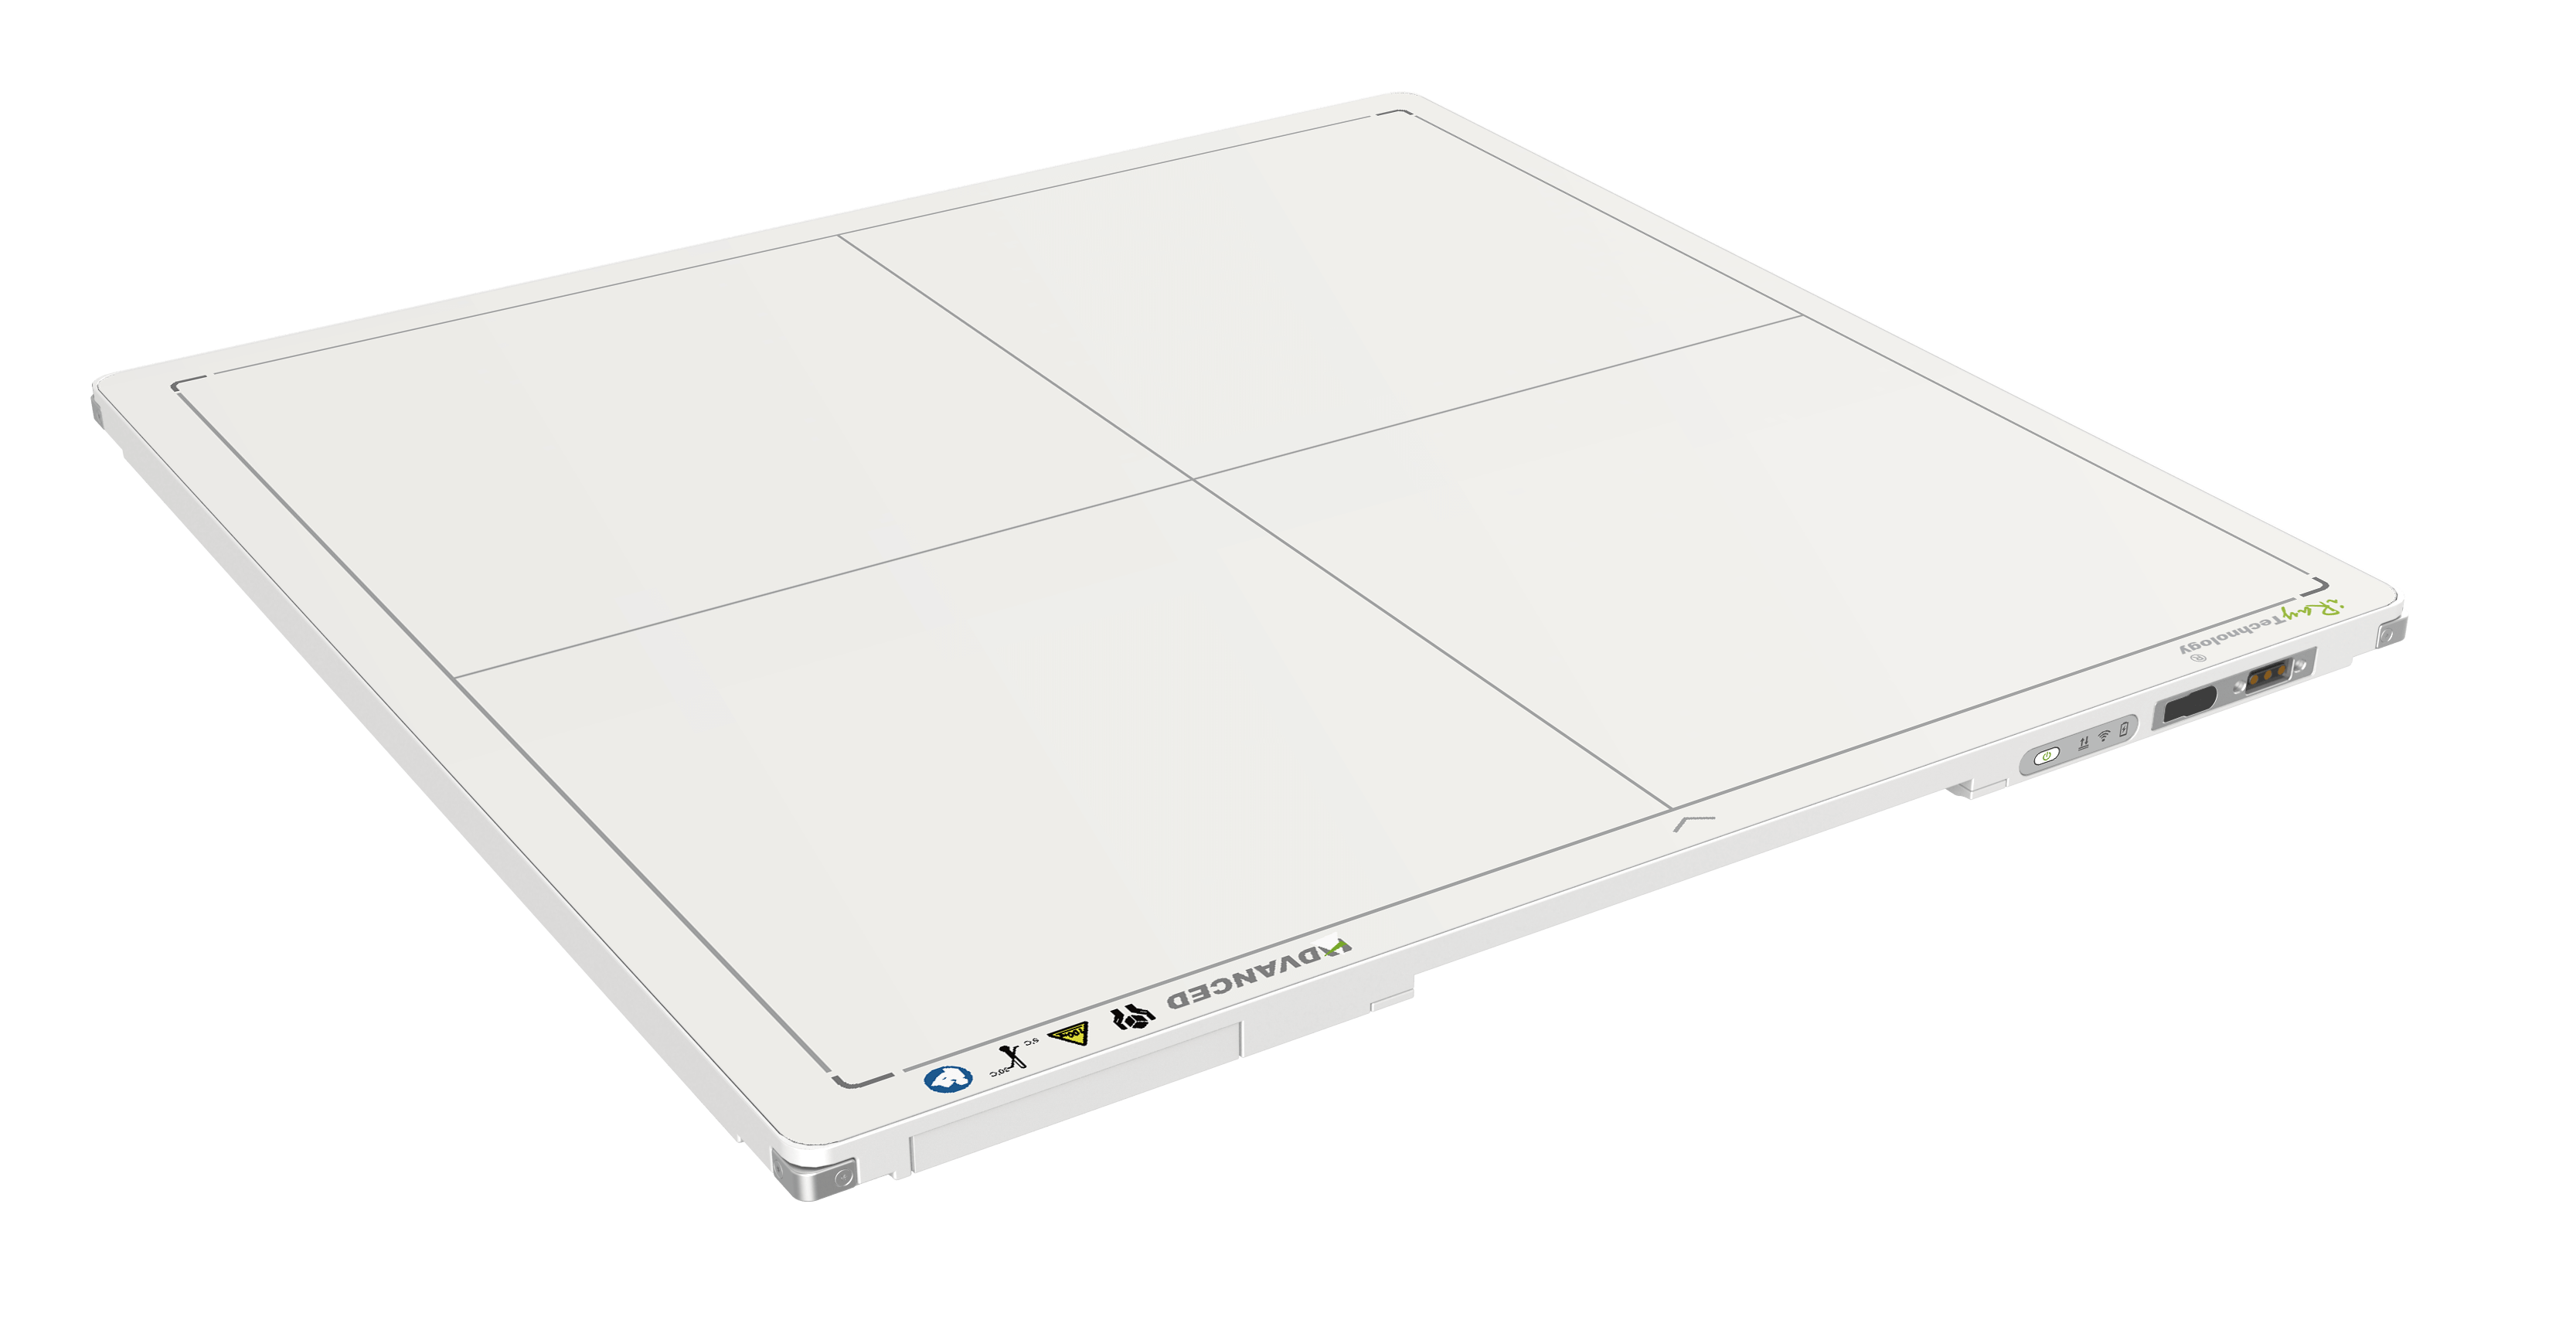

La société iRay propose des solutions innovantes en imagerie radiologique, alliant haute précision et qualité supérieure pour répondre aux besoins des hôpitaux et cliniques modernes.